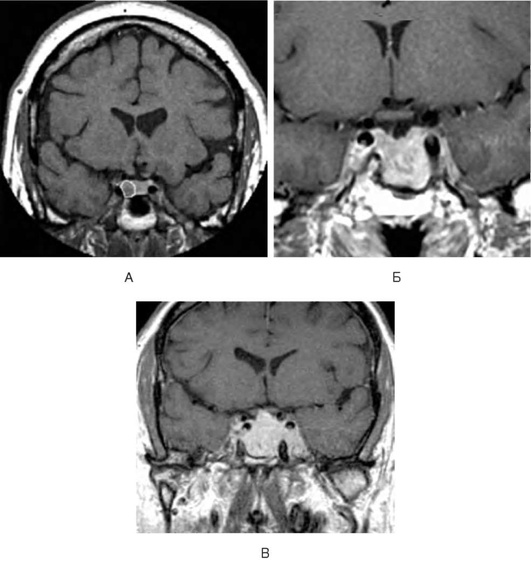

• МРТ и КТ головного мозга: спинномозговая жидкость определяется в полости седла; гипофиз обычно сдвинут к задней или нижней стенке седла, его вертикальный размер менее 3 мм.

Помимо основных изменений в хиазмально-селлярной области, МРТ позволяет выявить косвенные признаки внутричерепной гипертензии, сопутствующие этой патологии, - расширение желудочков и ликворосодержащих пространств.